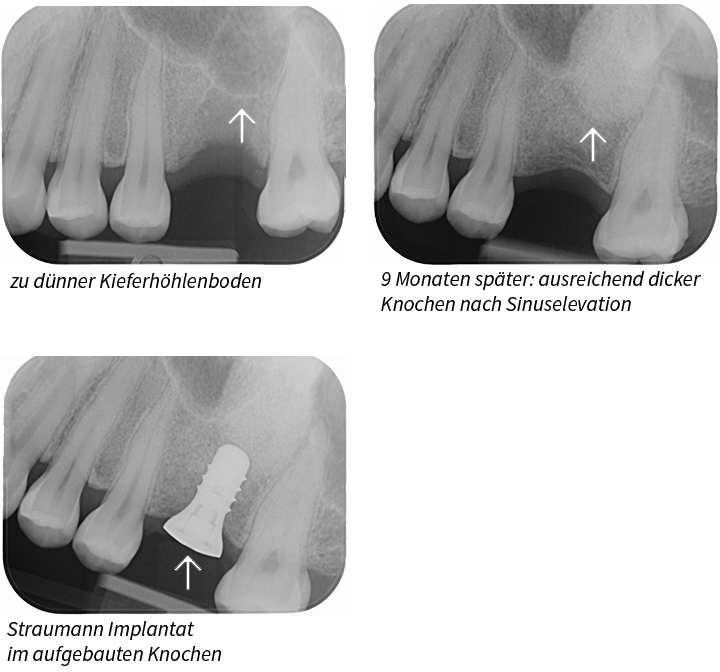

• Sinusbodenelevation ist eine spezielle Knochenaufbautechnik, da bei diesem Eingriff der Boden der Kieferhöhle angehoben und mit Knochenersatzmaterial aufgefüllt wird.

Das aufgebaute Areal wird mit einer Membrane (BioGide®) abgedeckt. Der neue Knochen entsteht in 6 Monaten und erst danach darf ein Implantat eingepflanzt werden.